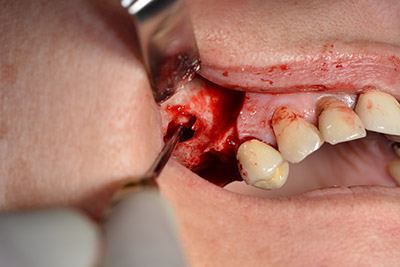

The fenestration was prepared at 35,000 rpm and then the nasal mucosa were prepared in the cranial direction (Fig. 13 to 14).

The implant was then placed and the bone built up. In this case, because of the size of the augmentation region, autologous bone chips, harvested with an osseous trap as drilling chips from implantation 16 and fenestration 14, were mixed with bone replacement material.

An absorbable membrane was used as the barrier in the buccal direction and covered the augmentation. Finally, saliva-proof sutures were placed (Fig. 15 to 19).